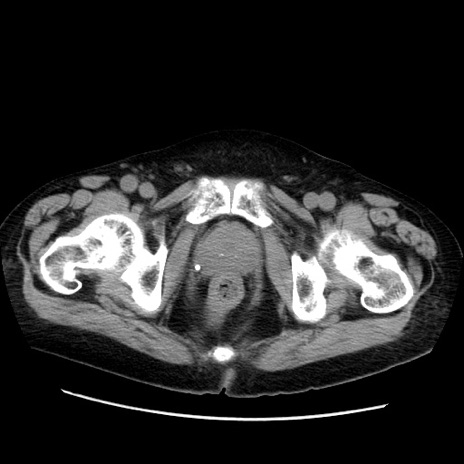

症例21(横断像)

【症例】70歳代男性

【主訴】腹痛

【現病歴】肝硬変・肝細胞癌にてかかりつけの方。約9時間前に食後より腹痛出現。症状が徐々に増悪し、嘔吐出現したため来院。

【既往歴】肝硬変、肝細胞癌(RFA、TACE後)

【身体所見】意識清明、表情苦悶様、BT 36℃、BP 129/78mmHg、P 88bpm、SpO2 97%(RA)、右上腹部から心窩部にかけて圧痛あり、反跳痛なし、筋性防御あり。

【データ】WBC 5800、CRP 0.16